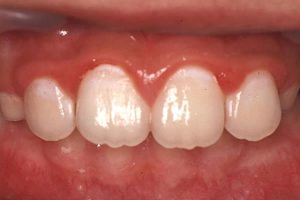

比較すべきものは、理想ではないのだ。

それでは何と比較すべきなのか?

この答えは“過去”である。

“過去”と比較すれば、良いところ探しがたくさんできる。

(図3)

患児の努力が見えてくる。

そのためにも写真で記録したり、カルテに一筆書いておく。

これが良いところ探しをするコツとなる。